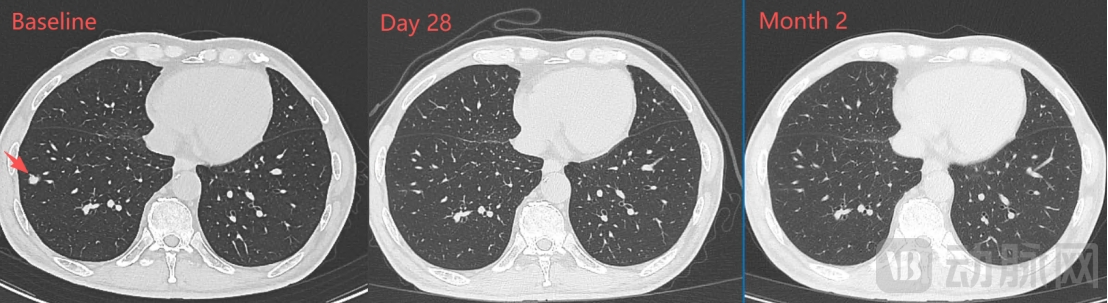

一个月的影像学检查显示:肝门区靶病灶明显缩小、肺部靶病灶基本完全消失,靶病灶直径之和从基线期的67mm缩小至43mm(下降35.8%),按RECIST1.1标准评估已达到部分缓解(PR);两个月的影像学检查显示:肿瘤病灶维持PR,且靶病灶直径之和进一步缩小至35mm(下降47.8%)。